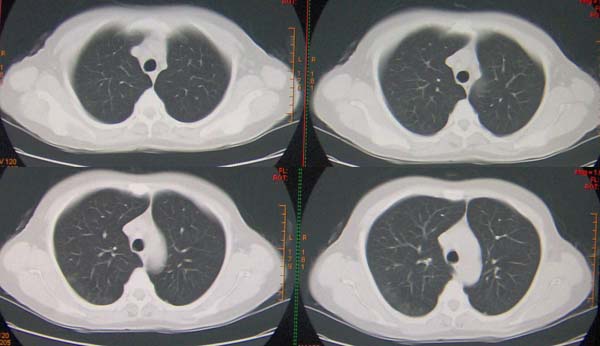

标题: CT9509:女,50岁,咳嗽,发热,38度, [打印本页]

标题: CT9509:女,50岁,咳嗽,发热,38度,

左肺下叶支气管呈囊状扩张。考虑支扩。

左肺下叶支气管呈囊状扩张。考虑支扩

左肺下叶支气管呈囊状扩张,考虑支扩。

左肺下叶支气管呈囊状扩张。考虑支扩伴感染

左肺下叶支气管呈囊状扩张,考虑支扩.

肺隔离症伴支扩(肺外型)或肺发育不良。

左肺下叶支气管呈囊状扩张,考虑支扩

左肺下叶囊状支扩伴感染